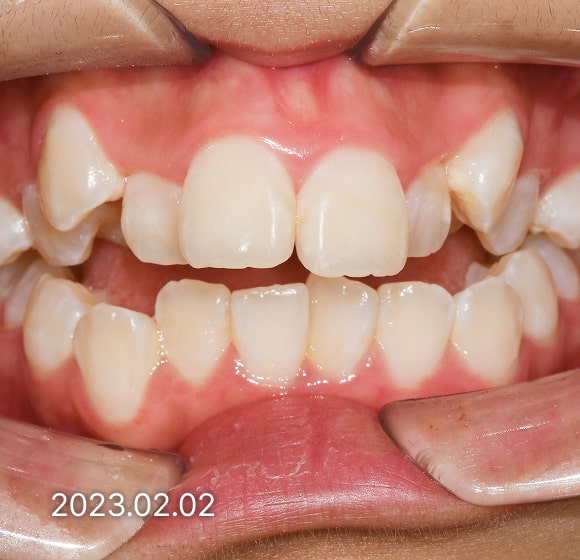

BEFORE / AFTER

전후 변화로 보는 치료사례

본 사진은 진심을담은치과교정과 치과의원에서

치료한 환자의 동일 인물 전·후 사진입니다.

개인의 구강 상태 및 관리 방법에 따라 통증 및 잇몸 염증,

턱관절 불편감 등의 부작용이 발생할 수 있습니다.

치료 전 치료 후

덧니, 삐뚤한 치열